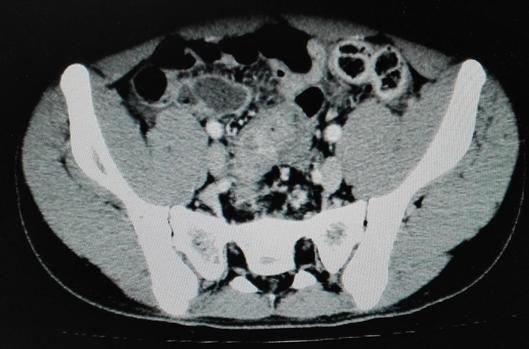

克唑替尼口服3日后,患儿腹部肿块逐渐缩小至4cm*3cm;口服第6天,腹部较前变软,未再排血便,神智较前转清,对答切题。体查:三凹征(-)中下腹部包块3cm*3cm。口服克唑替尼后第12天,患儿无胸水流出,能自行进食,腹部肿块缩小至2cm*2cm,患儿出院。患儿不规律口服克唑替尼一个月后,自行停药。复查腹部CT:腹腔大网膜肿块,互相融合,最大约7.1cm*4.7cm,较初诊外院片缩小。

2017年4月28日CT:腹膜、大网膜增厚、模糊,见多发结节,较大结节约12mm*10mm,增强轻中度均匀强化,结节较前缩小。腹盆腔多发结节,较前缩小。

2019年7月16日复查腹部彩超:腹主动脉旁多发淋巴结,大小约28mm*8mm,椭圆形,边界清,皮髓质分界不清,淋巴门未探及。肝脏、脾脏、胰腺、双肾、膀胱、前列腺未见明显占位病变。盆腔内未见明显占位性病变。双侧髂血管旁未见明确占位性病变。

停口服药治疗后3个月